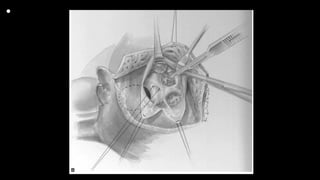

Figure 3 The traction sutures placed on the anterior and septal leaflets of the tricuspid

valve are essential in providing

exposure with minimal retractors in the field. Each suture is retracted directly toward

the surgeon, which pulls the

septum and VSD into view. A small right-angle retractor is then placed under the

anterior leaflet and pulled superiorly.

The anterior limb of the septal band is identified. A traction suture placed here can

help in the visualization of the out

flow tract and help in keeping the surgeon’s orientation. The traction suture placed in

the anterior limb of the septal

band, which marks the anterior edge of the VSD, can be very helpful in maintaining

orientation and exposing the distal

outflow tract. Anterior and superior to this point is the pathway to the pulmonary

valve, and the marking suture serves

as a useful frame of reference to avoid an incision into the VSD itself

• Figure 6 (A and B) Following relief of right ventricular outflow

obstruction, the VSD is closed. A continuous suture

technique is preferred, beginning at the juncture between the

anterior and posterior limbs of the septal band. The first

arm of the suture is placed along the anterior limb and around the

annulus of the aortic valve. The latter is exposed more

easily after the muscle bundles are divided. This suture passes into

the right atrium where the aortic and tricuspid valves

come together at the ventriculoinfundibular fold

• Figure 6 (C-E) The opposite needle is then used to anchor

the patch along the inferior limb of the septal band and along

the septal leaflet of the tricuspid valve in the standard fashion

using the usual techniques to avoid injury to the

conduction system. It is often necessary to weave the suture

under the chordal attachments of the tricuspid valve to

avoid distortion. The two ends of the suture are tied over a

small pericardial pledget. It is important to test the tricuspid

valve with saline to ensure that the valve is fully competent.

A suture placed at the anteroseptal commissure of the valve

is occasionally needed to reinforce this area.

•